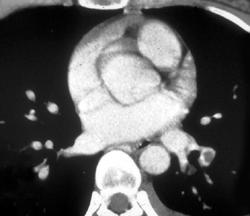

Pleural Lipoma